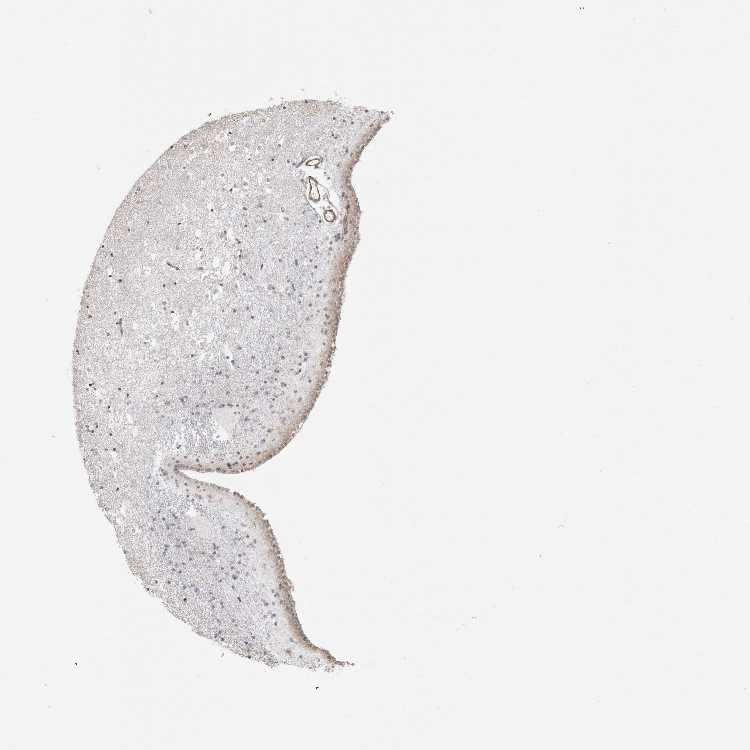

CAUDATE - Antibody stainingi

Antibody staining in the annotated cell types in the current human tissue is reported as not detected, low, medium, or high, based on conventional immunohistochemistry profiling in selected tissues. This score is based on the combination of the staining intensity and fraction of stained cells.

Each image is clickable and will lead to virtual microscopy that enables deeper exploration of all samples and also displays staining intensity scores, fraction scores and subcellular localization as well as patient and tissue information for each sample.

Antibody HPA023636Antibody HPA027962

Glial cells LowNot detected

Neuronal cells LowNot detected